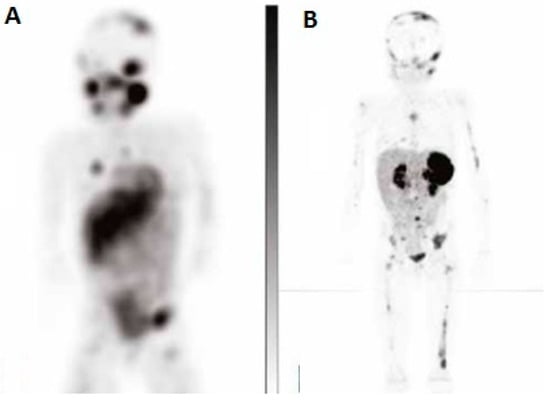

These preliminary results, although limited by the small cohort of patients and specifically referring to an adult population, encouraged further studies to better define the role of 64Cu-SarTATE in NB, especially with regards to the possibility of utilizing PET/CT for personalized provisional dosimetry before PRRT with 67Cu-SarTATE, thanks to the prolonged half-life of the diagnostic radiocompound allowing us to perform PET/CT at different time points, thus determining the in vivo estimation of SarTATE’s biodistribution and clearance. An example of PET/CT with 64Cu-SarTATE is reported in Figure 4.

Figure 4.

Neuroblastoma trial. On the left, a coronal SPECT view with 123I-MIBG in a metastatic NB (A) is reported; on the right, the same patient is imaged through PET with 64Cu-SarTATE (B) (Images courtesy of Clarity Pharmaceuticals).